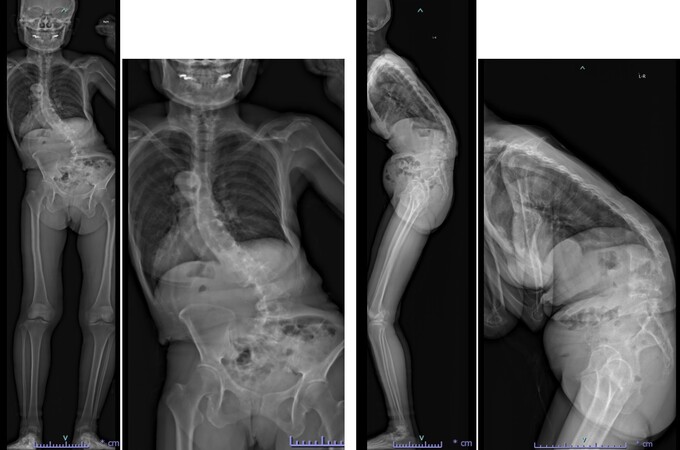

思春期特発性側弯症が高度に進行した症例です。最大側弯角度は113°であり、100°を超える側弯の手術は一般的に神経合併症が危惧されます。神経合併症を極力防ぐため、また侵襲を低減する目的で、同じ入院期間に2回に分けて段階的に矯正手術を行いました。1回目に最も側弯の強い箇所に対して側方から椎体間解離を行い、2回目に後方から全体のバランスが良くなるように慎重に矯正固定術を施行しています。

神経合併症はなく、術後の最大側弯角度は15°に改善(矯正率:87%)、背中の大きなコブも無くなっているのが分かります(赤矢印)。神経合併症が発生しないように慎重に手術を行うのは当然ですが、側弯を治すだけでなく横から見た姿勢を治すことにも留意しています。